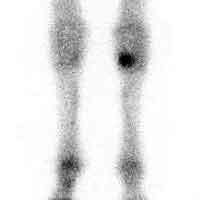

What diagnostic technique does the following image depict?

Scintigraphy